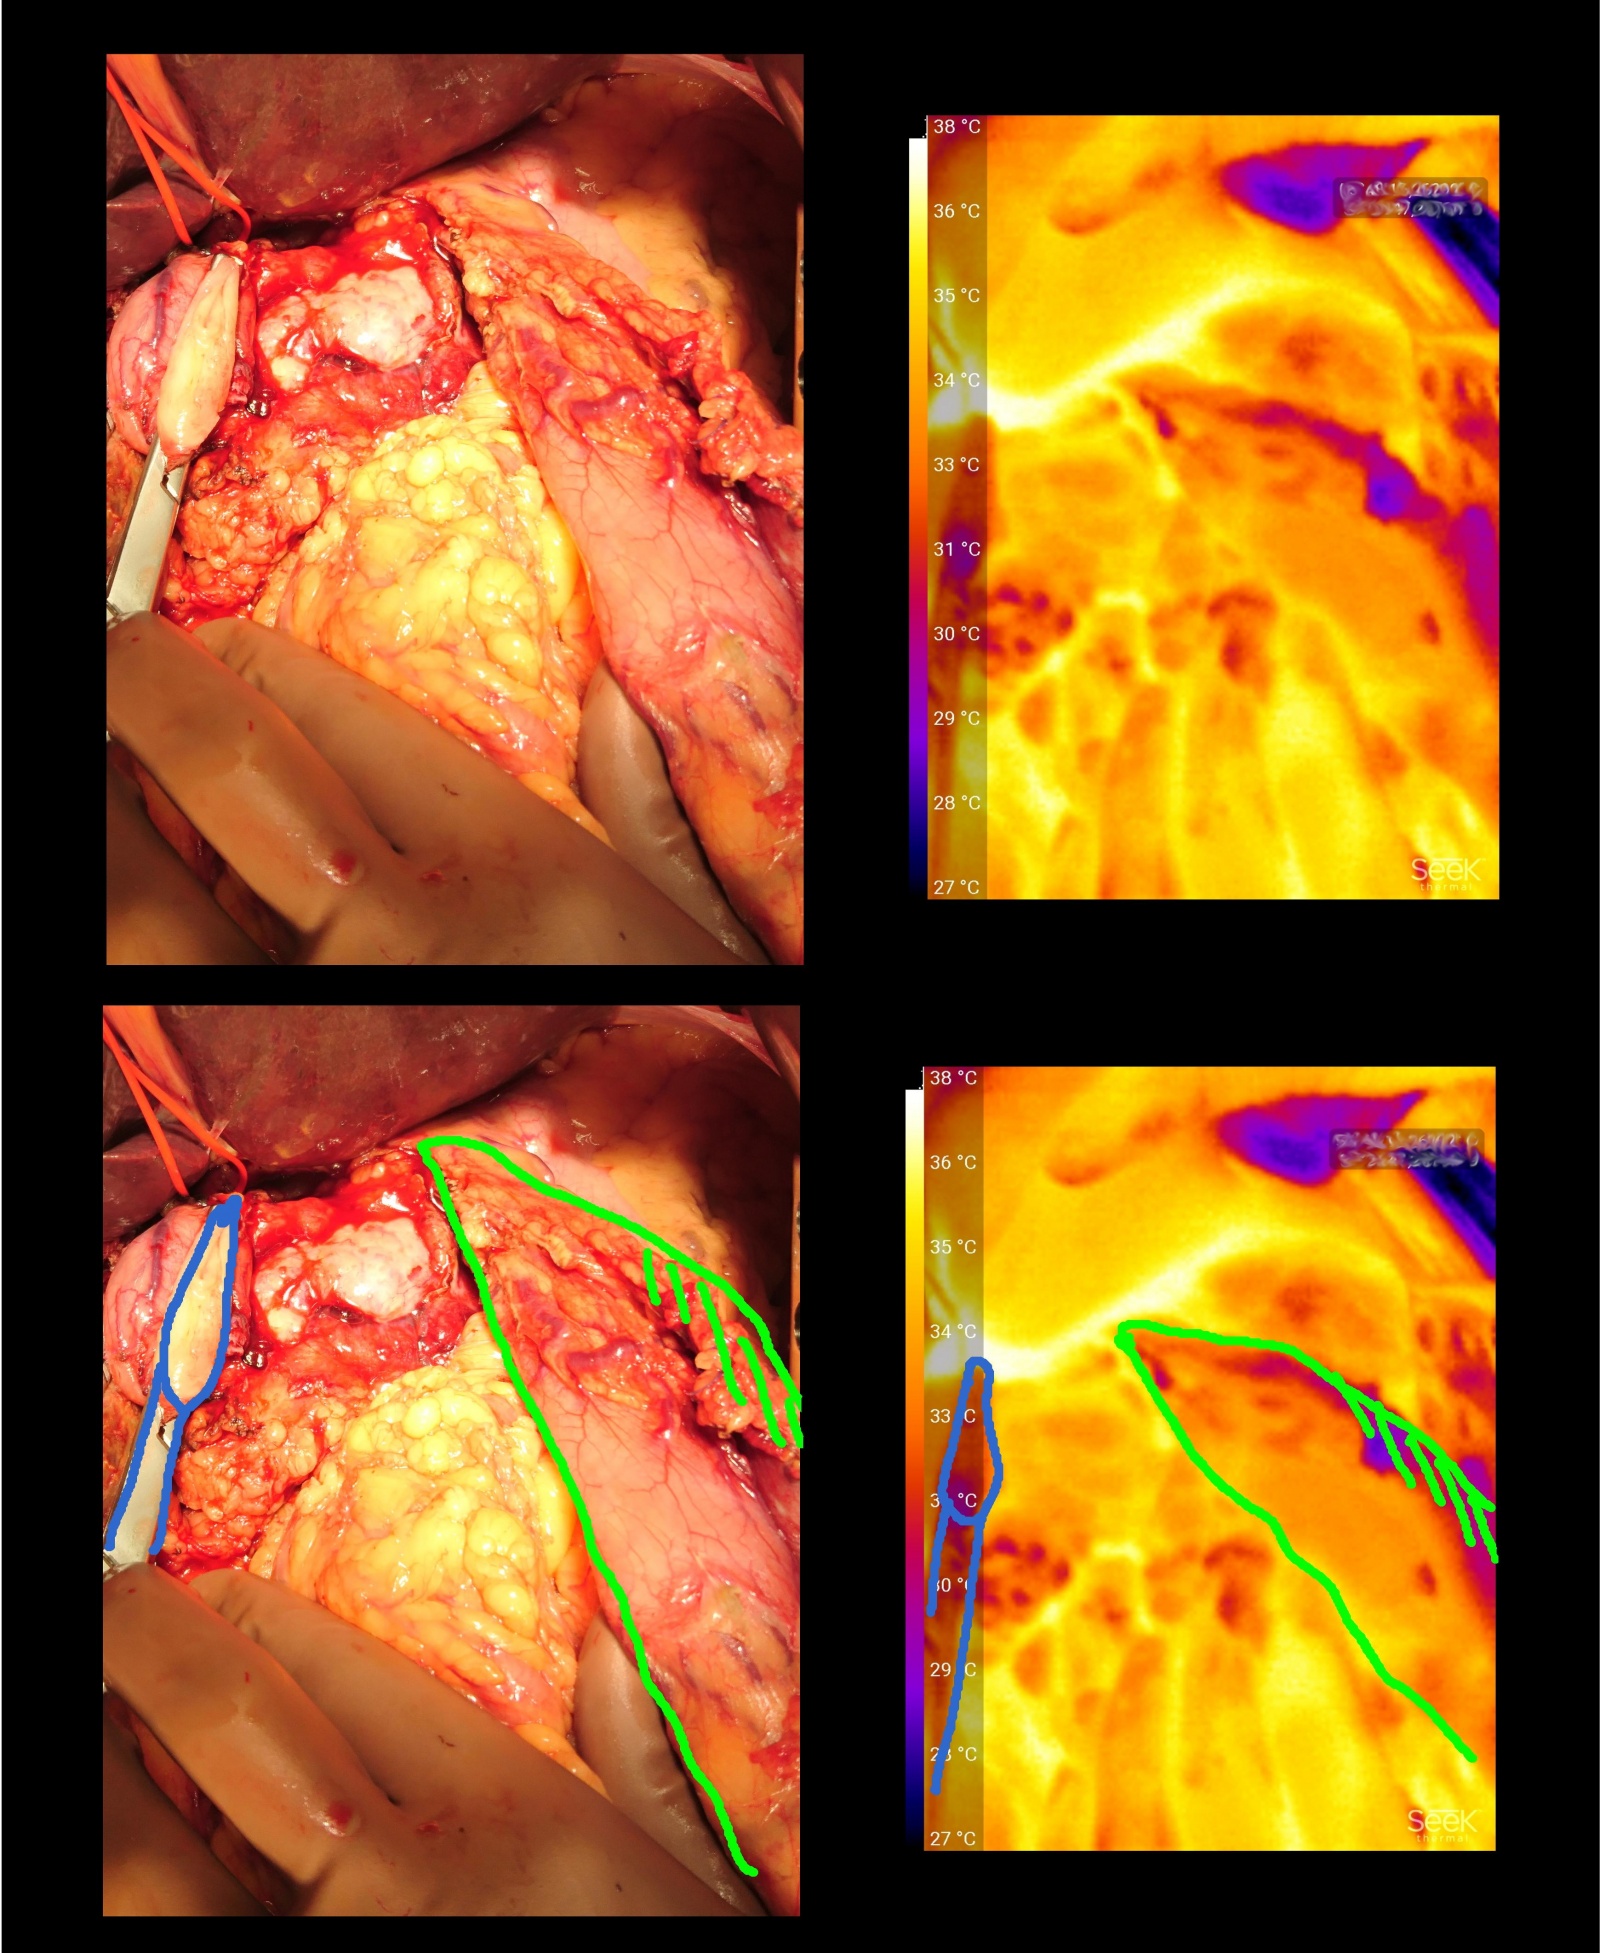

Доля «диагностических» исследований в хирургии до обидного мала. В большинстве случаев авторы пытались сосредоточиться на вопросах контроля нагревания окружающих тканей при работе различными видами коагулирующих приборов. Насколько сильно нагревается? Ну, по данным моих измерений, примерно так:

Черная линия — наконечник коагулятора, белая точка — рабочая поверхность на самом окончании наконечника + ткани, которых касается. Как видите, при средней температуре поверхности органов 31-35*С коагулятор греет до 55.

А вот так выглядит обработанный коагуляцией участок большого сальника (останавливали диффузное кровотечение).

Такие температурные режимы вполне соответствуют тому, что написано в статьях. Плохо это или хорошо — никто не скажет. В отдалении от крупных сосудов работа на таких температурах вполне допустима. Фичей надо правильно пользоваться, чтобы не было багов.